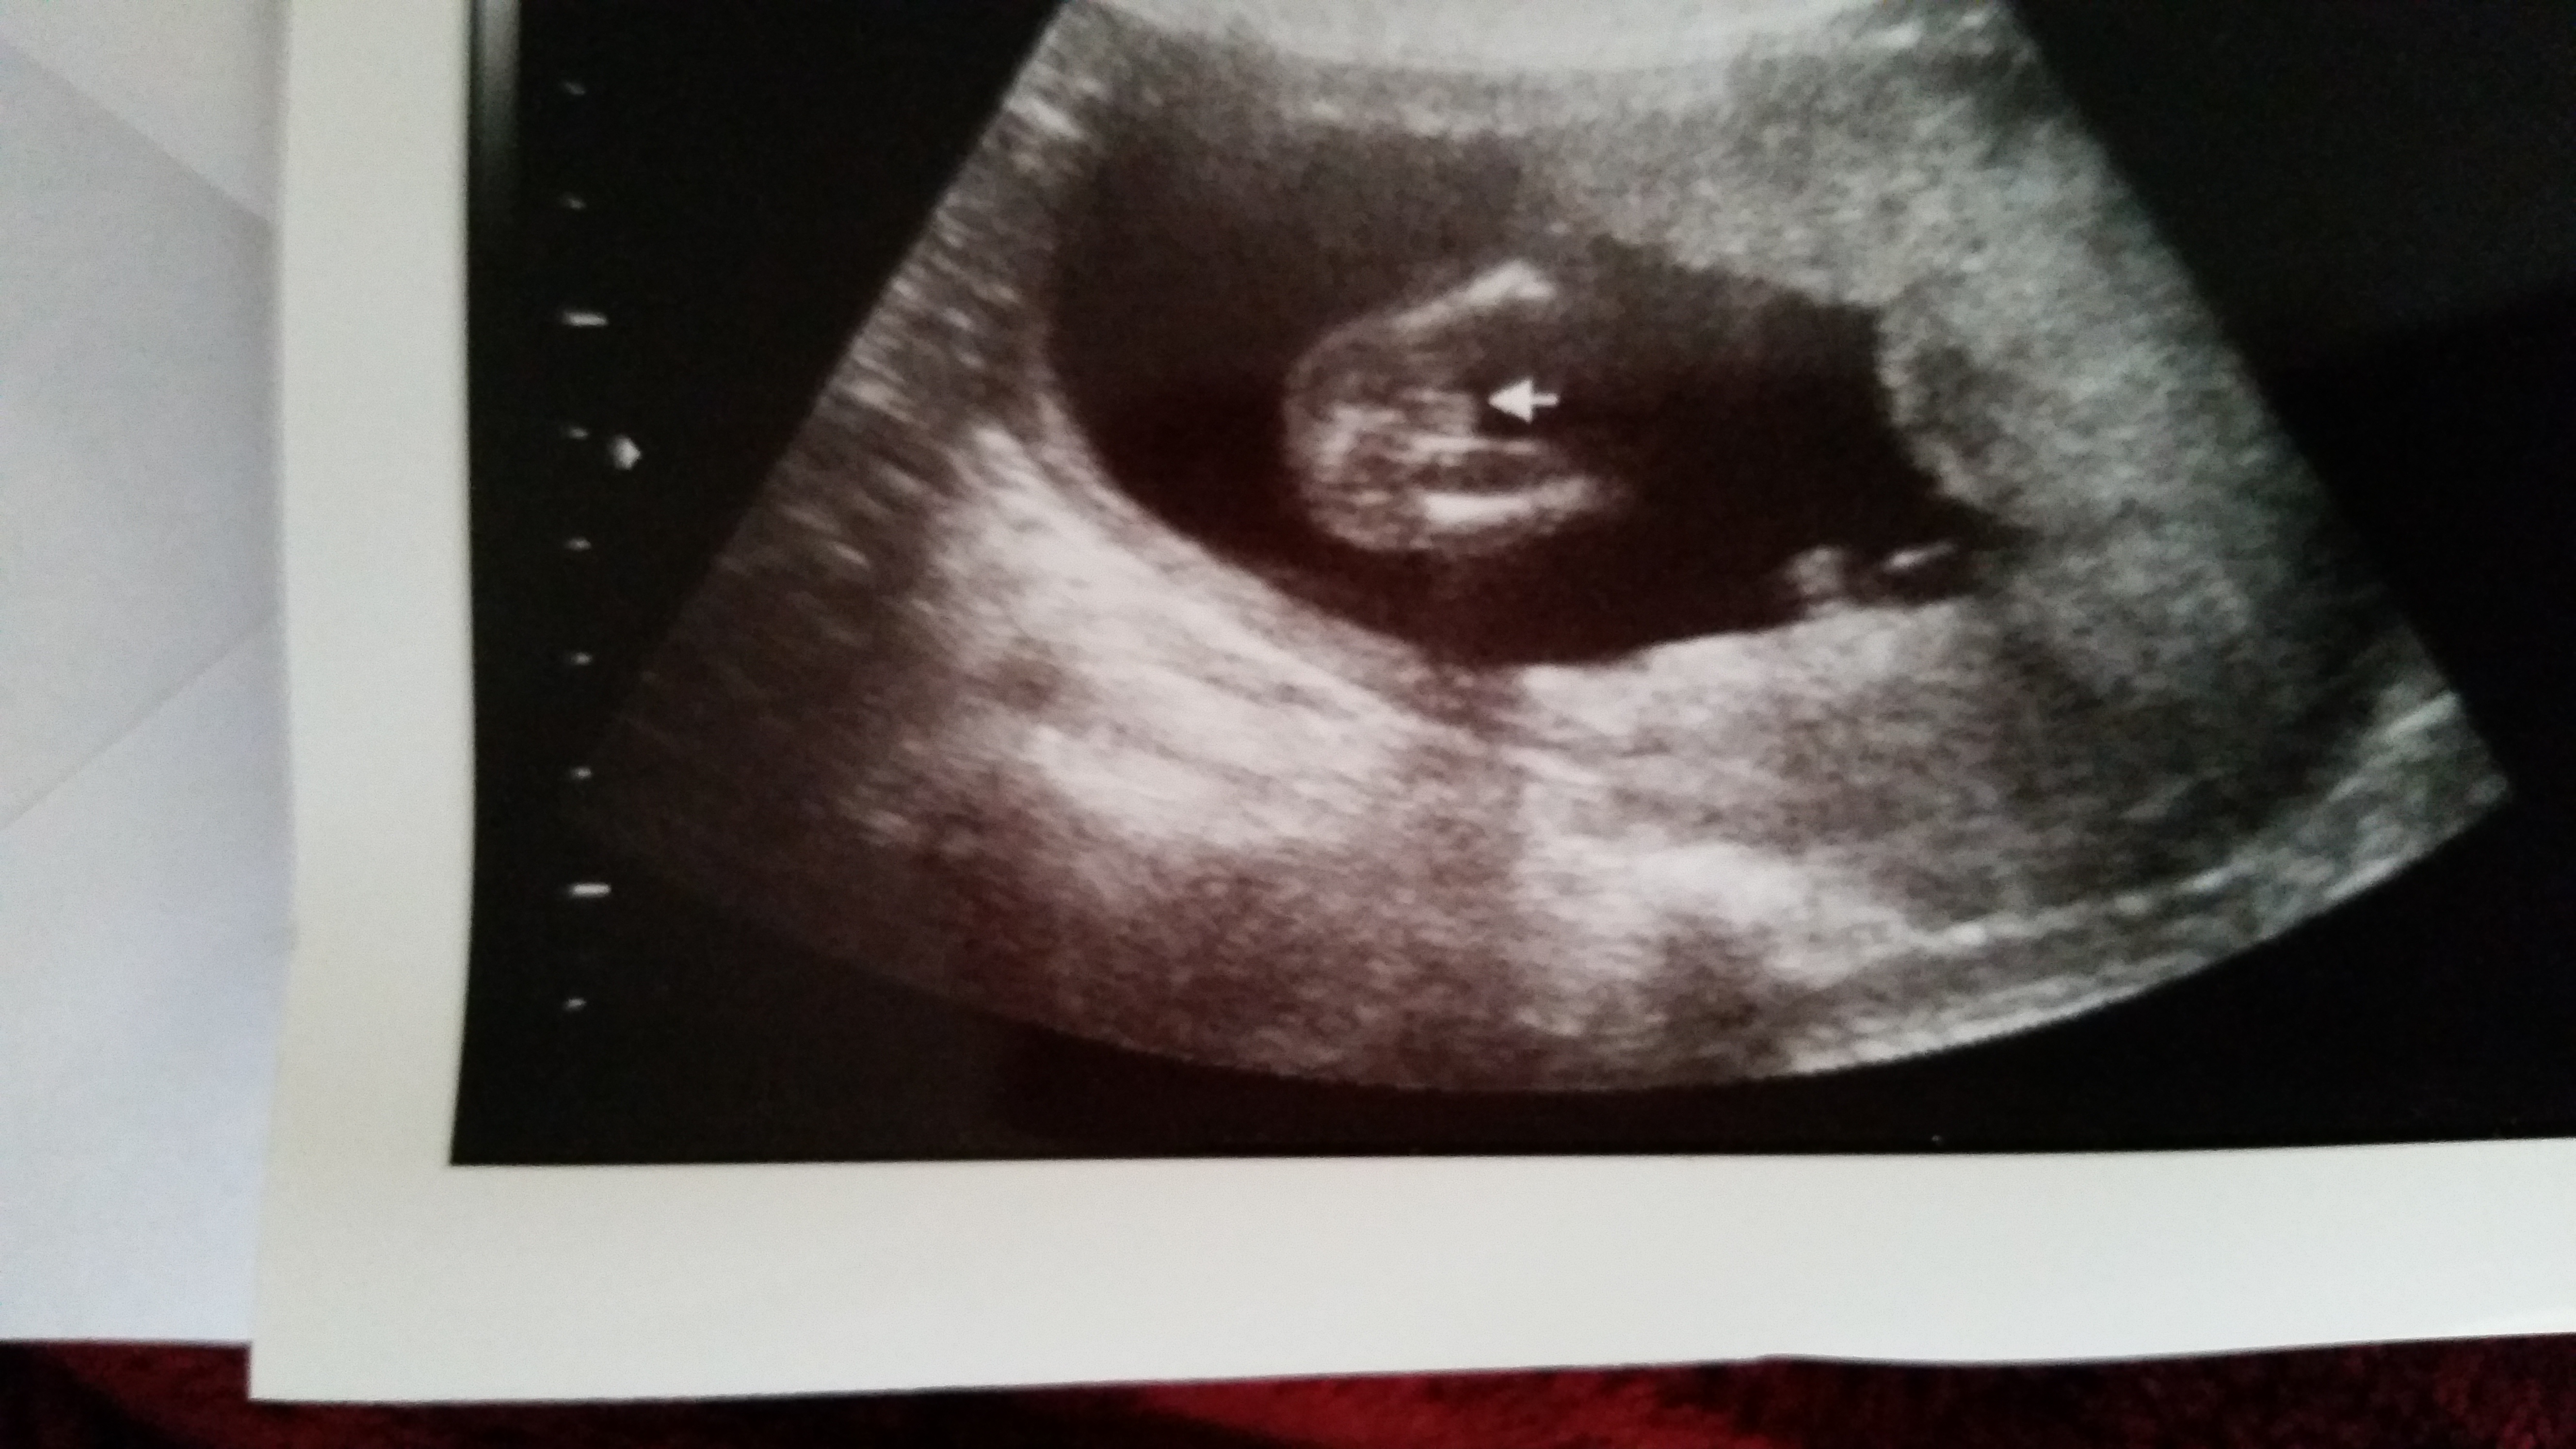

So I haven't been on here for ages but you ladies were helpful for me when I was swaying for pink and I got her!! I have a friend who just sent me this pic and wants to know my opinion. I know what I think, but I want to see what others think...... Please guess. I'm not sure how far along she is but I know it's +12wAttachment 22809